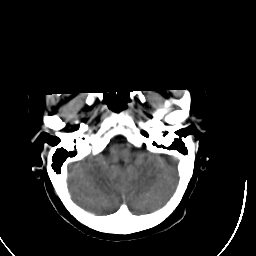

Stroke CT #3 -- Slice #3

[Home][Help][Clinical] Slice 3